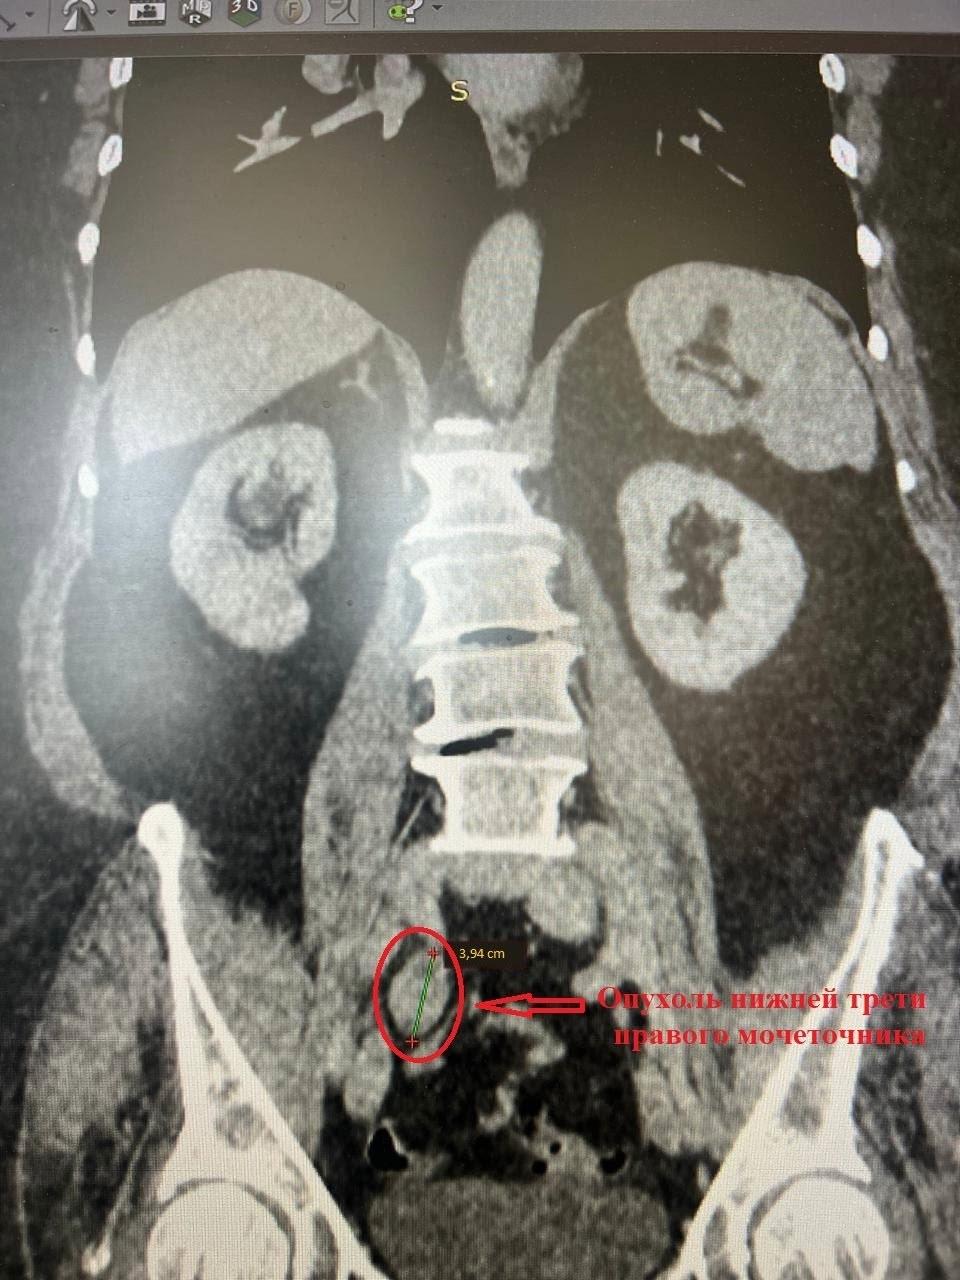

«Мы приняли решение в пользу органосохраняющей и малотравматичной операции. Нашей главной задачей было не только удалить опухоль размером 4 на 2 см, но и сохранить функцию почки, избежав инвалидизации пациентки. Поэтому мы выполнили лапароскопическую резекцию пораженного участка мочеточника с последующей реконструкцией по методике Боари», – объяснил заведующий урологическим отделением Коломенской больницы, врач высшей квалификационной категории, доцент кафедры урологии Рязанского государственного медицинского университета им. акад. И.П. Павлова, кандидат медицинских наук Иван Собенников.